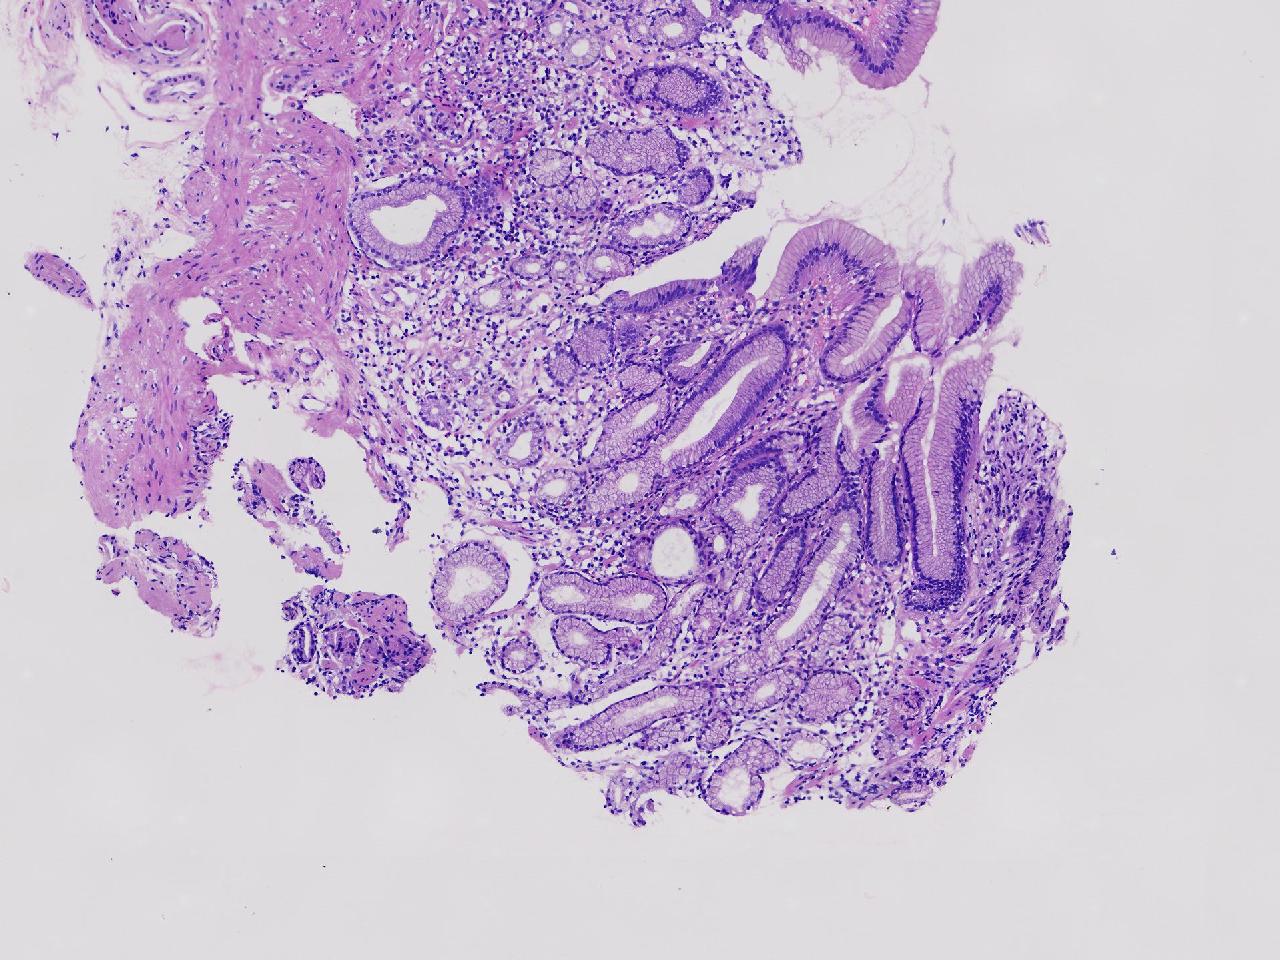

男,76岁。胃体前壁见1纵行溃疡,底覆白苔,周围粘膜充血水肿,于病变周边取材3块。

胃体前壁活检

灰白色不整形软组织3块,直径均0.2厘米。

粘膜中度慢性炎伴糜烂,固有层淋巴细胞聚集